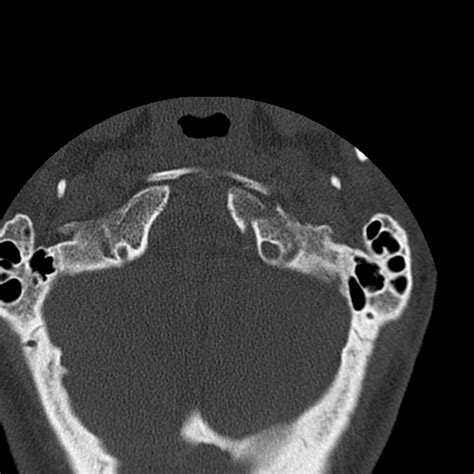

• Computed Tomography (CT) Scan: This is the gold standard for diagnosing occipital condyle fractures. CT scans provide detailed images of the bony structures and can help identify the location and extent of the fracture.